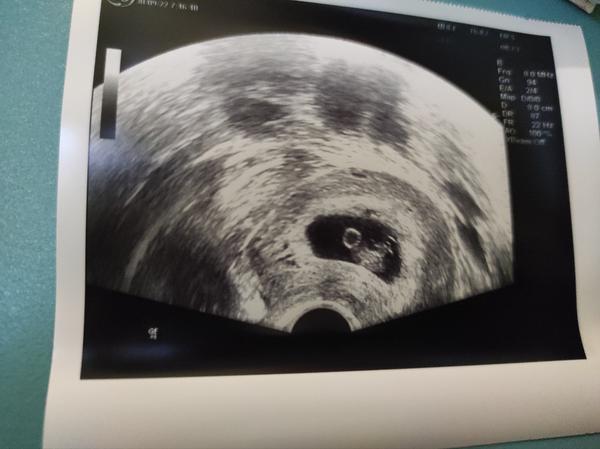

@terezie262 Já myslím, že je ještě určitě brzy, pokud jsi 6+něco... Já byla na první kontrole 5+6 a doktorka jen zkontrolovala, jestli se nejedná o mimoděložní těhotenství, ale zatím ještě vůbec nic neviděla... Pak jsem šla na další kontrolu 7+6 a to už bylo krásně vidět i srdíčko (viz foto). Držím pěsti, ať za týden také bije ❤

poslední těhotenství, které bohužel nakonec stejně skončilo ZT, jsem měla na první kontrole 6+5 embryjko 8mm a srdeční akci. předchozí těhotenství a první kontroly jsem na kontrolách kolem 6+2 mívala obdobný nález, gestační a žloutkový váček, bez embrya. doktorka vždy řekla, že to může být ok, že může jít o mladší těhotenství, ale já vždycky věděla, kdy ovulace byla a že mladší těhotenství není. osobně si myslím, z mých zkušeností (mám za sebou 2x ZT bez srdeční akce, 1x SP a 1x ZT po zjištění srdeční akce), že by v tom 7tt mělo být vidět už víc než jen váčky, minimálně ten embryonální pol. taky záleží, jak dobrý má doktorka ultrazvuk. samozřejmě je varianta, že ovulaci jsi měla později, vajíčko se déle zavrtávalo...pak tu stále je šance, že se jedná o prosperující těhotenství. držím palce, ať je to tvůj případ a za týden na kontrole uvidíš bublinku s pulzujícím srdíčkem.

6+3, srdíčko embryo 6mm, jinak nic moc vidět nebylo, bohužel u mě je vždy špatná viditelnost 🙄